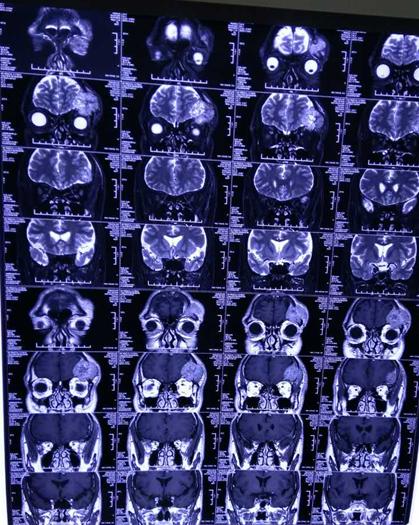

第四军医大学唐都医院神经外科五病区贾栋主任门诊仔细为李大爷进行查体,了解患者病史后建议首先进行影像学检查,后经头颅MRI显示:患者左侧额部可见一大小约4.3CMX4.2CMX3.5CM包块,呈稍长T1,稍长T2信号,其内可见点片状短T1,长T2混杂信号影,病变与邻近脑膜关系密切,邻近颅骨呈溶骨性骨质破坏,并突破颅骨向外生长及向眶内生长,左侧上直肌受压,左侧额叶受压,病变与额叶间可见弧形长T2脑脊液信号影,确诊为脑膜瘤,建议尽快进行手术治疗。

患者影像学资料: